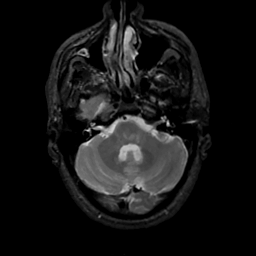

MR Study #7, March 24, 1991 -- Slice #11

[Home][Help][Clinical][Tour 1][Tour 2] Slice 11